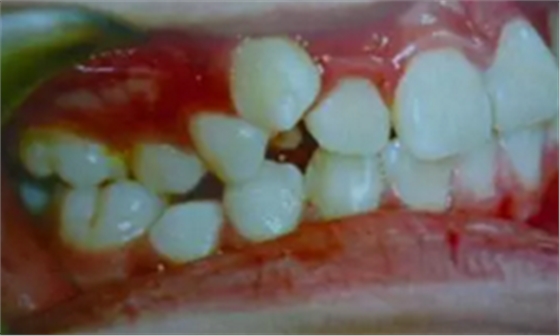

牙齒需要矯治的患者,往往牙齒和排列和咬合關(guān)系多會(huì)出現(xiàn)錯(cuò)亂,那些錯(cuò)亂的牙齒即使不拔除,它也是沒(méi)有功能的,因?yàn)樗蛯?duì)頜的牙齒咬不上。

并且,這些排列不正常的牙齒很難清理干凈,容易在它的周?chē)媪艉芏嗍澄餁埩?,久而久之就形成蛀牙,最后也是一拔了之。我們醫(yī)生拔牙的時(shí)候有一定選擇的,一般是拔除那些壞牙、沒(méi)有功能的牙。